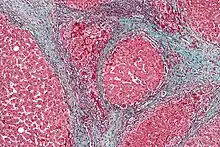

Cirrhosis

In addition to virus-related cirrhosis described above, other causes of cirrhosis can lead to HCC. Alcohol intake correlates with risk of HCC, and the risk is far greater in individuals with an alcohol-induced cirrhotic liver.[37] There are a few disorders that are known to cause cirrhosis and lead to cancer, including hereditary hemochromatosis and primary biliary cirrhosis.[38]